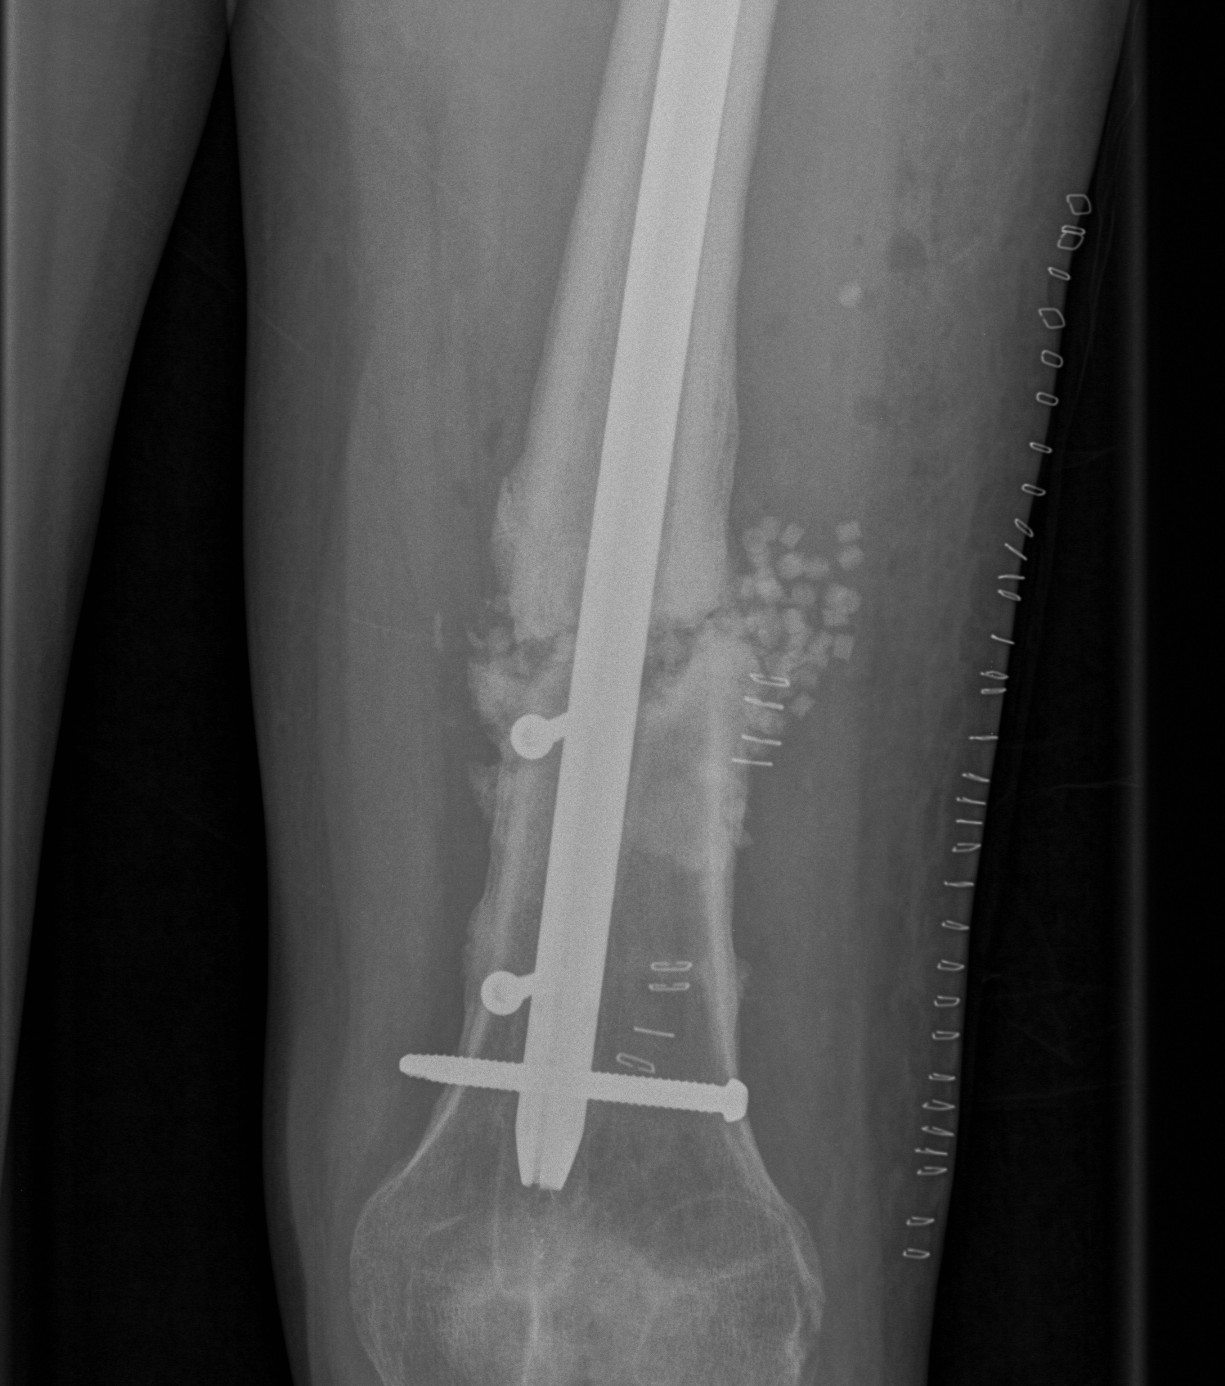

2. NOF (Neck of Femur) + Femoral shaft fracture

Must pay attention first to meticulous NOF ORIF

Options

1. Pin and Plate NOF / Retrograde Nail

2. Pin and Plate NOF / Plate femur

3. Reconstruction Nail

- difficult to anatomically reduce NOF

- increased incidence NOF non union

Results

Ostrum et al. CORR 2014

- 95 cases treated with proximal screws / sliding hip screws inserted first

- retrograde IMN second

- 98% union rate femoral neck

- 91% union rate femoral shaft